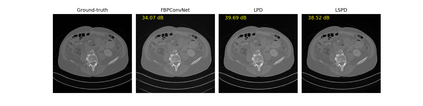

We propose a new type of efficient deep-unrolling networks for solving imaging inverse problems. Conventional deep-unrolling methods require full forward operator and its adjoint across each layer, and hence can be significantly more expensive computationally as compared with other end-to-end methods that are based on post-processing of model-based reconstructions, especially for 3D image reconstruction tasks. We develop a stochastic (ordered-subsets) variant of the classical learned primal-dual (LPD), which is a state-of-the-art unrolling network for tomographic image reconstruction. The proposed learned stochastic primal-dual (LSPD) network only uses subsets of the forward and adjoint operators and offers considerable computational efficiency. We provide theoretical analysis of a special case of our LSPD framework, suggesting that it has the potential to achieve image reconstruction quality competitive with the full-batch LPD while requiring only a fraction of the computation. The numerical results for two different X-ray computed tomography (CT) imaging tasks (namely, low-dose and sparse-view CT) corroborate this theoretical finding, demonstrating the promise of LSPD networks for large-scale imaging problems.